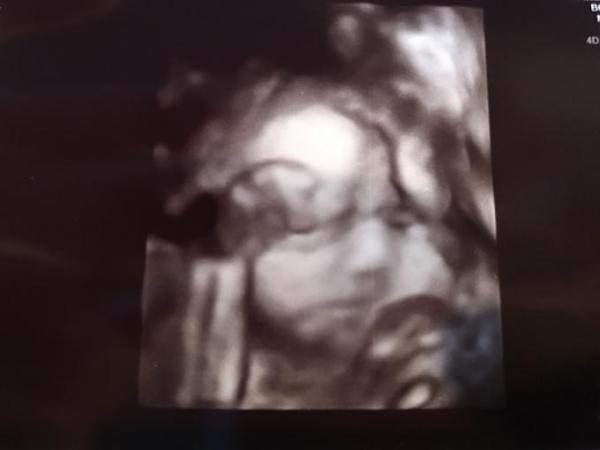

Hallo ihr Süßen Bis zurück von meiner FÄ. Zuckertest war eklig aber mit super Werten - hat sich also gelohnt . Muss jetzt Eisen nehmen und habe Annanasextrakt verschrieben bekommen, weil ich so viel Wasser einlagere . So, 3D US war echt schön, obwohl sich unser Schatz echt gestreunt hat und ständig die beiden Hände vor dem Gesicht hatte. Aber es war trotzdem toll. Nächster Termin in 4 Eichen ist schon mit CTG Wahnsinn, oder? Meine Hebi wollte die Vorsorge eigentlich ab der 30. SSW alleine machen, aber da hält meine FÄ nichts von. Gerade weil sie meine Werte der Trombos kontrollieren möchte. So, dann geht es ab der 30. SSW alle 2 Wochen zur FÄ und alle 2 Wochen zur Hebi ! Das war es von mir. Habt noch einen wunderschönen Abend

Das Bild sieht doch ganz gut aus :) Freue mich über die guten Nachrichten!

Glückwunsch zum tollen Ergebnis und süßen Foto!

Tolle Nachrichten und ein mega süsses Bild